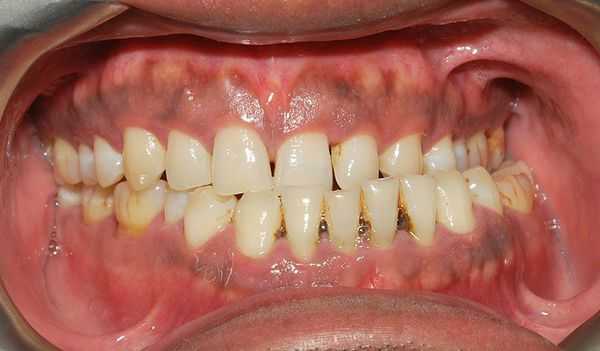

Нередкий признак прогрессирующей патологии с осложнениями — это некариозные поражения твёрдых тканей зубов: клиновидные дефекты, сколы эмали, патологическая стираемость зубов, недолговечность ортопедических конструкций или пломб.

Нередко пациенты жалуются на прикусывание слизистой оболочки щёк и отмечают неправильное произношение звуков речи.

Клинический осмотр лица помогает выявить выраженную асимметрию и пропорциональные несоответствия. При осмотре полости рта определяют тип перекрёстного прикуса. Оценивается состояние твёрдых тканей зубов: обнаруженные клиновидные дефекты, патологическая стираемость, сколы эмали, а также короткий срок службы пломб может косвенно свидетельствовать о наличии окклюзионных перегрузок, тем самым подтверждая поставленный диагноз. Слизистая губ и щёк нередко имеет отпечатки зубов из-за накусывания слизистой в месте перекрёстного положения зубов.